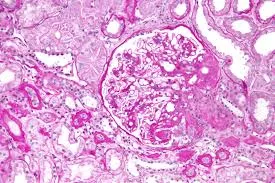

Meu paciente com NIgA tem proteinúria entre 0,5–1,0 g/dia, já está em iECA e iSGLT2: devo pensar em imunossupressão?

Proteinúria entre 0,5–1,0 g/dia na NIgA não é benigna e já se associa a maior risco de progressão renal. A evidência atual reforça <0,5 g/dia como alvo terapêutico, valorizando proteinúria cumulativa e tendência ao longo do tempo. Antes de pensar em imunossupressão, o foco deve ser otimização máxima da terapia de suporte e estratificação cuidadosa de risco.